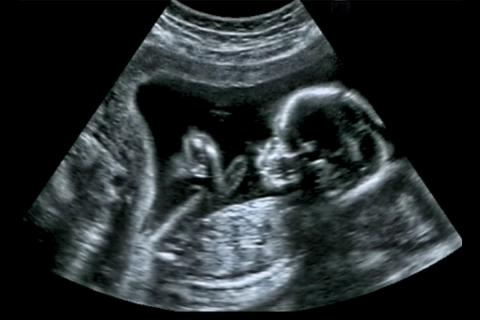

High-risk pregnancies are one of the leading causes of maternal deaths in developing countries. Draper is working with the Bill & Melinda Gates Foundation to address the issue with a new kind of ultrasound imaging system. (Credit: Creative Commons)